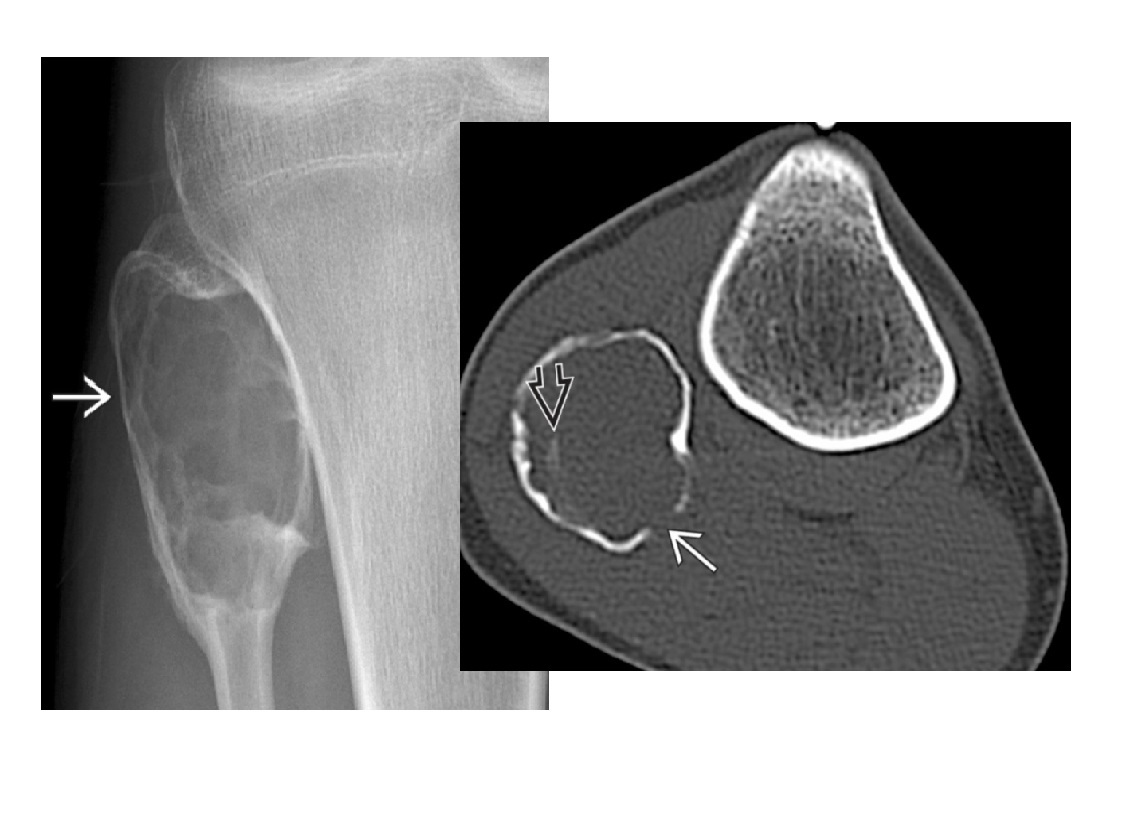

Osteochondroma

points away from the joint

Pedunculated lesion arising from surface of bone with continuity of normal cortex and marrow

Metaphysis/metaphyseal equivalents (rarely diaphysis)

Multiple =

Diaphyseal aclasia/Multiple Hereditary Exostoses - Metaphysis region of tubular bones of extremities

Cap > 1.5cm ??? chondrosarcomatous transformation